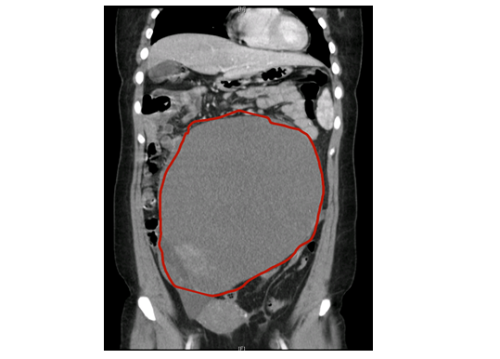

妇产科一区科主任、副主任医师黄佼介绍,患者阴式彩超及盆腔CT提示:盆腹腔巨大囊性肿块,大小约30cm,占据整个盆腹腔,结合其他检查结果考虑“左侧卵巢癌”。考虑到患者年轻,未生育,手术团队随后为患者行保留生育功能的卵巢癌全面分期术,所幸术后病检结果为左侧卵巢高分化粘液性囊腺癌IA期,无需进一步放化疗,患者术后恢复良好,出院后继续随访。

盆腔CT检查提示左侧卵巢巨大肿块大小约30CM